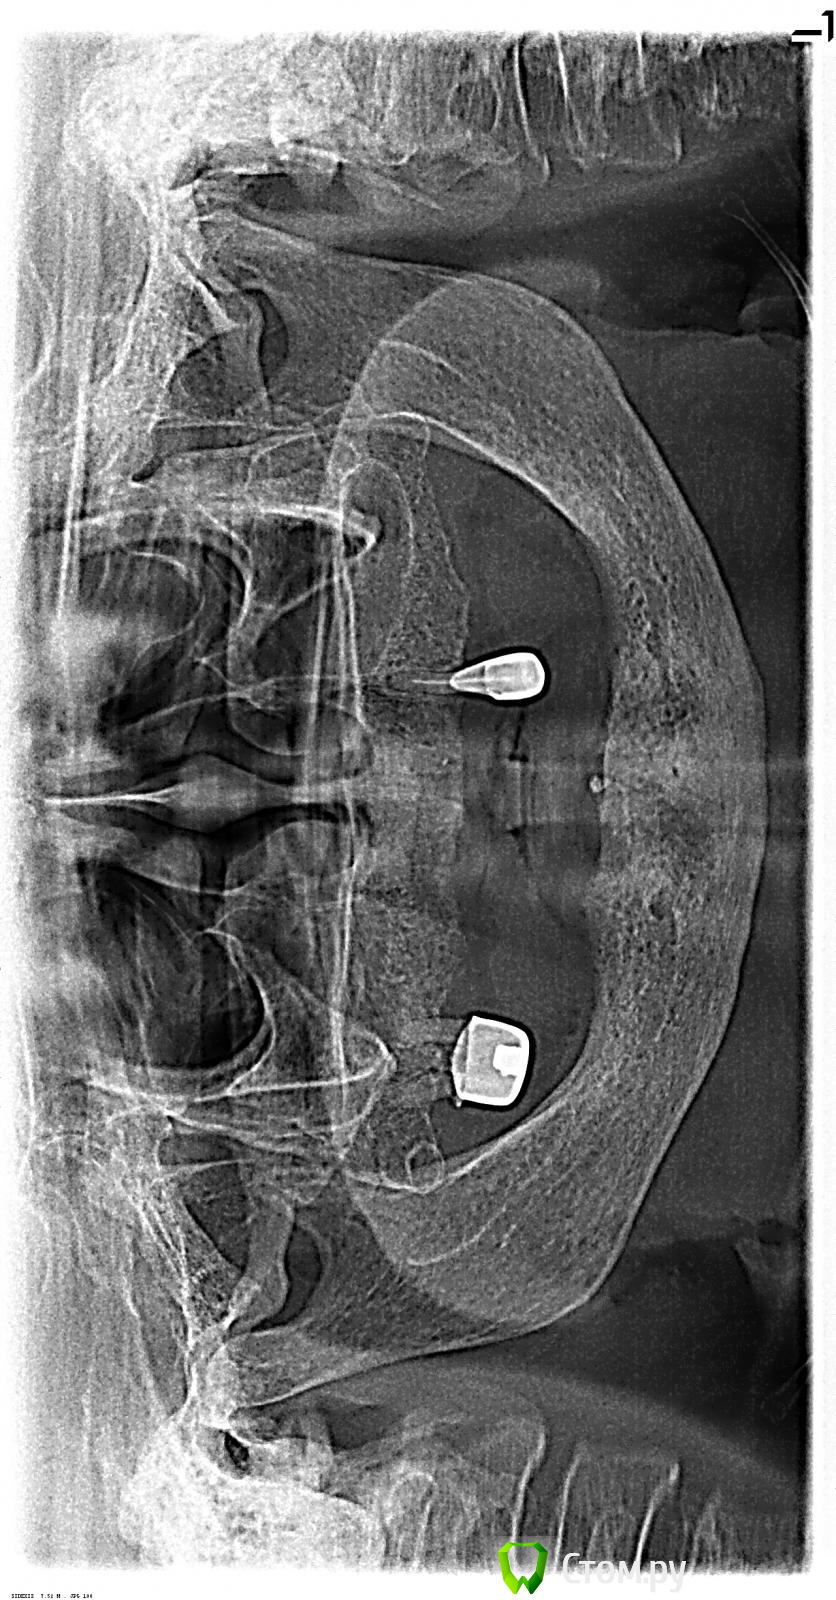

ввассилюй Опубликовано 1 октября, 2014 Поделиться Опубликовано 1 октября, 2014 Пацинтка готова на съемник. Опыт у меня не большой. Мысли такие - поставить во фронт 2 импланта и сделать съемный протез. Ссылка на комментарий

kriokov Опубликовано 1 октября, 2014 Поделиться Опубликовано 1 октября, 2014 (изменено) http://www.imageup.ru/img283/1894829/12.jpgставьте четыре, потом локаторы, если бюджет ограничен (про н\ч ведь разговор)К администраторам-- тему видимо во врачебный надо перенести Изменено 1 октября, 2014 пользователем kriokov Ссылка на комментарий

faity Опубликовано 1 октября, 2014 Поделиться Опубликовано 1 октября, 2014 я бы тоже 4 поставил, и на верх тоже, а хлам в плевашку 2 Ссылка на комментарий

an_ver Опубликовано 2 октября, 2014 Поделиться Опубликовано 2 октября, 2014 4 на в/ч ..потом или шаровые абатменты,локаторы,балка..короче что потянет Ссылка на комментарий

an_ver Опубликовано 4 октября, 2014 Поделиться Опубликовано 4 октября, 2014 Низ - 4 шт. в межментальном с немедленной нагрузкой.Согласен.Есть и у меня такая бабуля Ссылка на комментарий